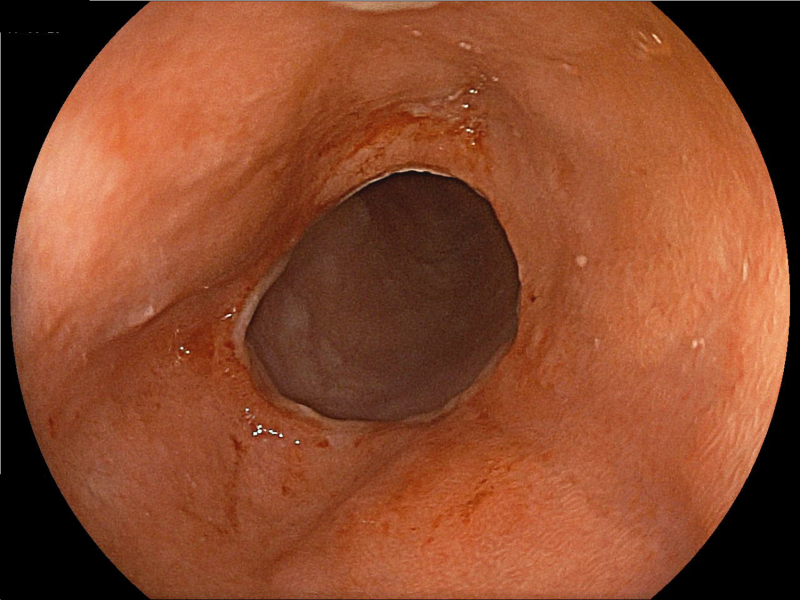

Distal to the Bulb, a False Tulip

Fotografia